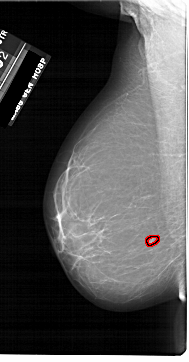

A_1860_1.RIGHT_MLO

RIGHT_CC LINES 6001 PIXELS_PER_LINE 3331 BITS_PER_PIXEL 12 RESOLUTION 43.5 NON_OVERLAY

FILE: A_1860_1.LEFT_CC.OVERLAY

TOTAL_ABNORMALITIES 1

ABNORMALITY 1

LESION_TYPE MASS SHAPE IRREGULAR MARGINS ILL_DEFINED

ASSESSMENT 4

SUBTLETY 3

PATHOLOGY BENIGN

TOTAL_OUTLINES 1

BOUNDARY